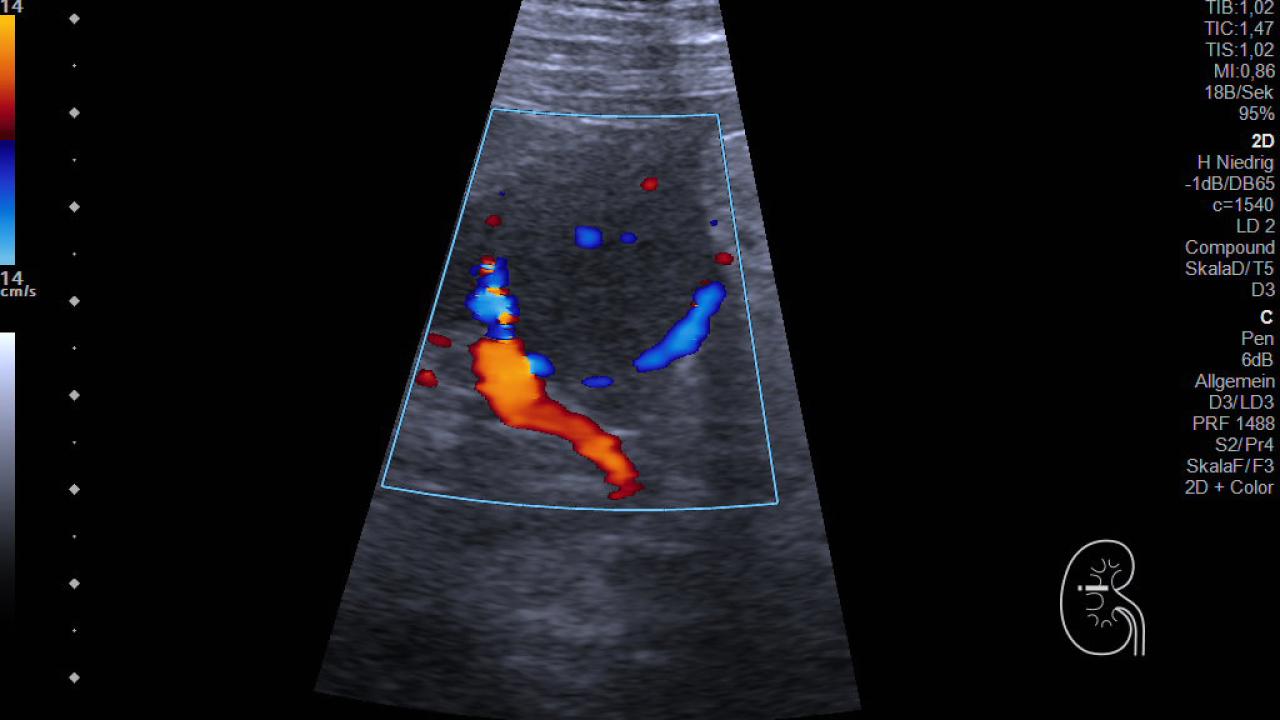

Die optimale Diagnostik und Therapie von Nierentumoren erfordern ein individualisiertes und interdisziplinäres Vorgehen. Daher hat sich die Klinik für Urologie gemeinsam mit dem internistischen Ultraschall-Labor der Abteilung für Nephrologie und dem Institut für Radiologie zum interdisziplinären Nierentumorboard zusammengeschlossen.

Hier wird für jede Patientin und jeden Patienten individuell die Diagnose und beste Behandlungsstrategie in einem interdisziplinären Nephrologisch-urologisch-radiologischen Konsens festgelegt, wobei die Befunde in der Konferenz aufwendig mit CT/MRT und mit Ultraschall in Parallelprojektion unter Berücksichtigung von Klinik und Komorbiditäten diskutiert werden.

So können wir für jeden Fall das bestmögliche Vorgehen festlegen. Ein besonderer Schwerpunkt ist das Auftreten von Nierentumoren in Transplantatnieren, die ein besonders gut abgestimmtes Vorgehen in Zusammenarbeit mit der Transplantationschirurgie erforderlich machen.